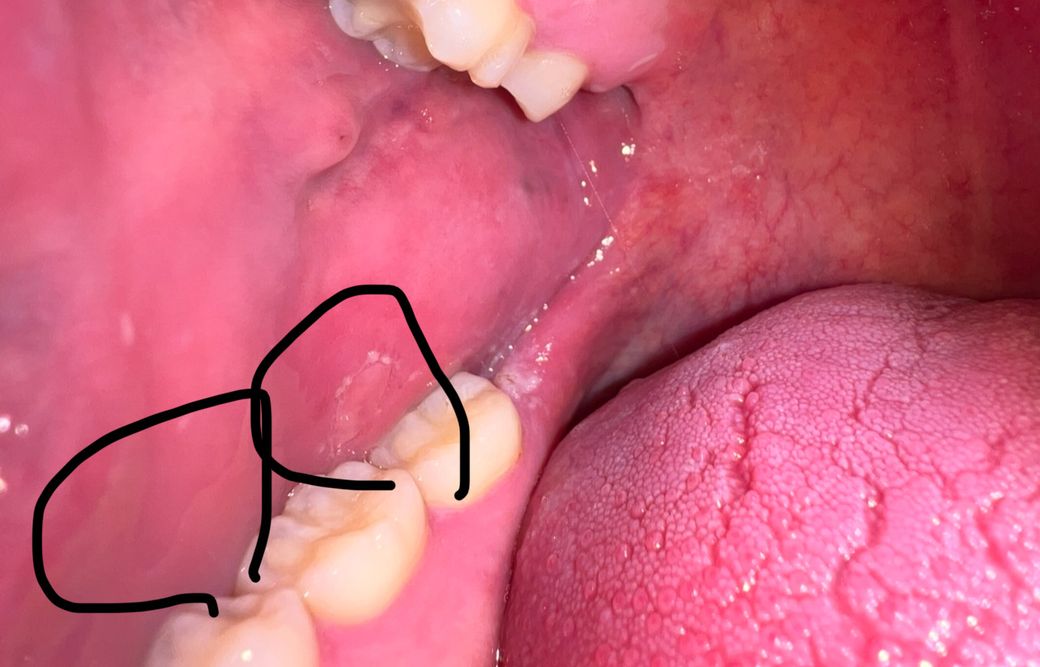

입에 병변 확인 한번만 부탁드립니다 ㅜㅜ

몇일전에 찢어졌던 상쳐를 제가 손으로 만져서 살이 더 까졌거든요 선생님들 혹시 상처가 아무는 괴정일까요 아니면 구강암 병변 뭐 이런걸까요 너무 걱정되서 여쭙습니다 혹시 동그라미 친 부분 구강암 병변일지 걱정되서 이렇게 여쭤봅니다 그리고 동그란병변 옆에 얼룩같은 지도모양 저거는 왜 저런지도 궁금해서 답변 부탁드리겠습니다 ㅜㅜ

특별히 악성병소의 양상은 아니나 구강내과가 진료과로 있는 치과가서 한번 진단 받아보시기 바랍니다.